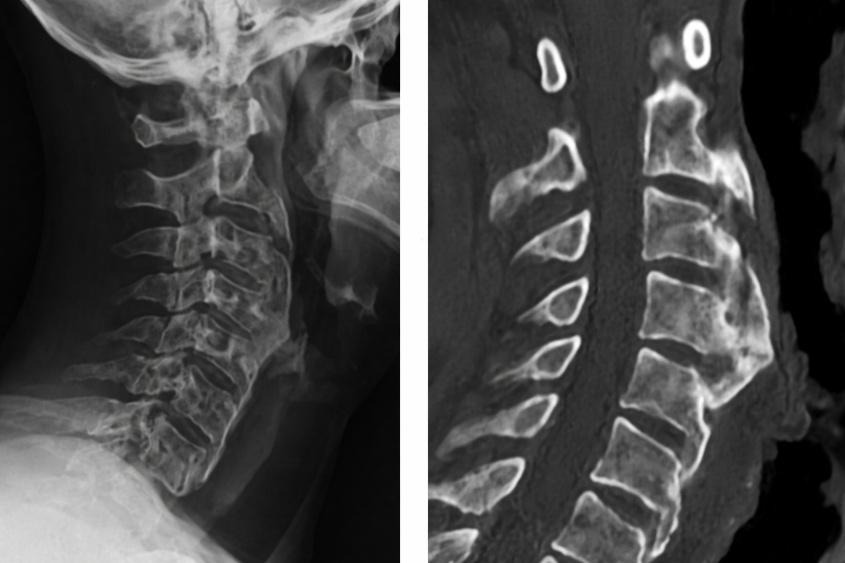

O sistema auditivo integra aferências somatossensoriais do trigêmeo e das raízes cervicais superiores já no núcleo coclear dorsal. Clinicamente, movimentos cervicais, mandibulares, posturais, respiratórios ou oculares podem modular o zumbido. Esse fenômeno, frequentemente tratado como subtipo etiológico, pode ter maior relevância prognóstica.

Propõe-se incorporar a modulação somatossensorial como variável prognóstica, investigando sua presença por história clínica e testes padronizados (movimentos cervicais, mandibulares, oculares, entre outros). Com base nisso, podem-se definir três perfis: zumbido não modulável (maior chance de habituação), parcialmente modulável (habituação mais lenta) e fortemente modulável (baixa taxa de habituação espontânea, com necessidade de intervenção direcionada).

Do ponto de vista terapêutico, propõe-se deslocar o foco do mascaramento para a estabilização do sinal, em três níveis complementares: periférico (correção de disfunções cervicais e mandibulares, postura e tônus), central (exposição controlada, indução de supressão por repetição e estabilização de padrões neurais) e emocional (redução da reatividade límbica). O objetivo é reduzir a variabilidade do zumbido, favorecendo previsibilidade e habituação.